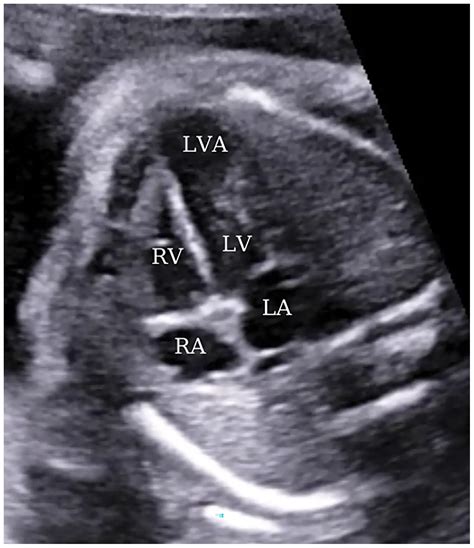

• Echocardiogram: This uses sound waves to create images of the heart, allowing doctors to visualize the aneurysm and assess its size and location.

• Heart Failure: The weakened ventricle may not be able to pump blood efficiently, leading to heart failure.

• Thromboembolism: Blood clots can form in the aneurysm and travel to other parts of the body, causing blockages in blood vessels.